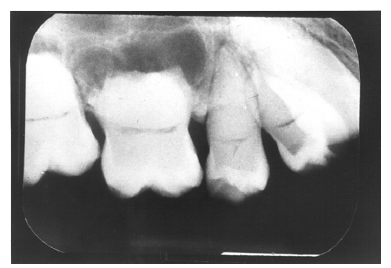

Dentin caries extends into the tooth dentin and can be recognized by noting the focal loss of dentinal radiopacity. Most commonly, this darkened dentin is located beneath carious enamel and, typically, the lateral dimension of the dentinal involvement exceeds that of the associated enamel caries (Figure 3). Dentin caries may be discerned interproximally, on the occlusal surface, buccally/lingually, or on root surfaces.

Figure 3 - Dentin Caries

Figure 3